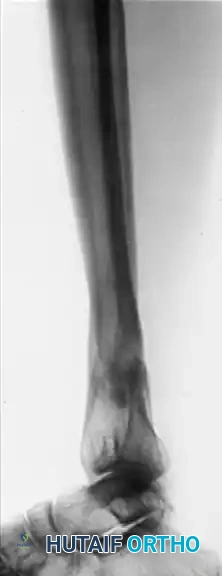

Image

Postoperative AP and Lateral radiographs demonstrating solid tibial union with restoration of normal mechanical alignment. An asymptomatic nonunion of the fibular osteotomy persists, which is a common and clinically benign finding.